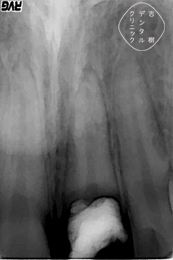

歯が割れてしまった場合、マイクロスコープやCTなどを用いて精密検査を行います。検査の結果、歯の1/3程度の長さの根が残っていれば、治療できる可能性があります。

「エクストルージョン」は、矯正治療の一種で、歯茎に埋もれている歯の根を外に引っ張り出す治療法です。必要な長さの根が歯茎の中に残っていれば、エクストルージョンによって歯の根を外側に引き出し、ここに被せ物を装着します。

③エクストルージョンができるだけの歯根が確認できた